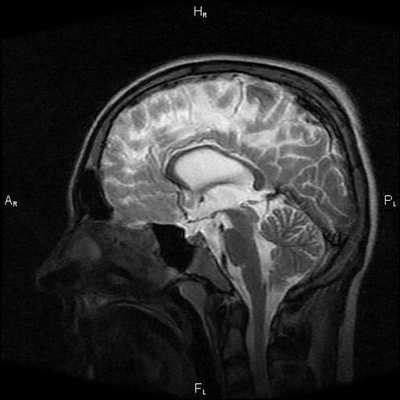

Этот высокотехнологичный метод визуализации анатомических структур, не связанный с воздействием рентгеновского излучения, позволяет безопасно и с высокой эффективностью определить этот диагностический показатель у пациента. МР-диагностика определяет высокое внутричерепное давление по следующим «маркерам»: частично пустое турецкое седло, расширенные оболочки зрительных нервов, уплощенные задние части глазных яблок, щелевидные желудочки.

При МРТ головного мозга установлено: МРТ признаки хронической недостаточности мозгового кровообращения; выраженная открытая внутренняя гидроцефалия, свидетельствующая о признаках атрофических изменений в головном мозге.

![МРТ снимок внутричерепного давления]()